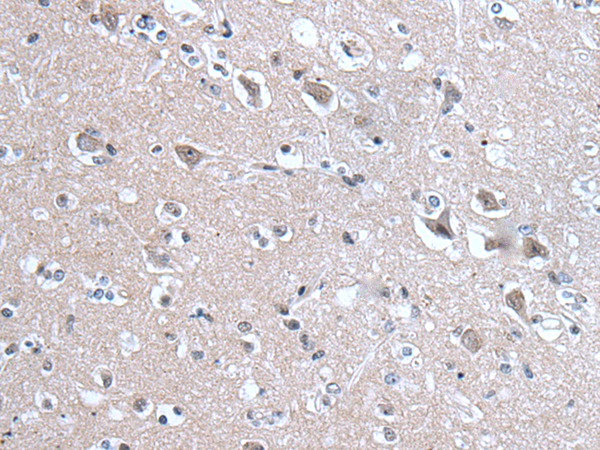

分类: 科研抗体货号: P12861别名:应用: IHC反应种属: Human, Mouse, Rat